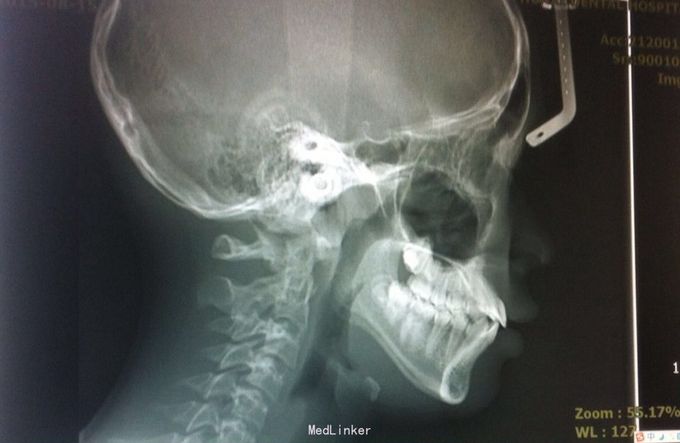

前牙散在间隙 安氏一类

恒牙期 磨牙中性关系 前牙覆合覆盖关系正常 A1B1之间1mm间隙

安氏一类 不拔牙矫治,直丝弓矫治器,排齐整平上下牙列,关闭前牙散在间隙,矫治后磨牙中性关系,前牙正常覆合覆盖,维持现有面型